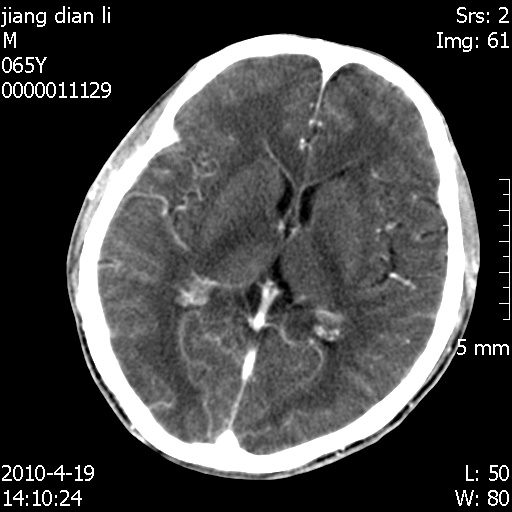

老年男性,突发左下肢无力1天,其余有价值的检查都没有。平扫ct值大约60hu,增强后ct值没什么改变,请大家讨论一下这个病例是什么?说明诊断理由。

左小脑、右大脑顶叶多发圆形高密度病灶,其周环状低密度影。考虑多发脑出血。隔期观察。

今天上班后发现病人前天复查(4月18日发病,19日初诊,22日复查),三个病灶均明显增大,边缘仍旧清楚,水肿加重,右侧脑室基本闭塞。

基于这样的表现,不知大家有什么看法?(临床其他检查我还没有追踪)

我想:如果是肿瘤出血的话,一般不会导致体积明显改变,水肿又进一步加重;如果是出血灶,那么现在应该正好是水肿加重的时候,还是比较符合,但是为什么边缘又是这样的特点?